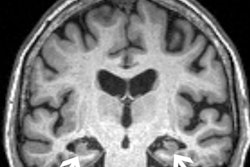

In fact, the increased use of these treatments in trials led to the discovery of ARIAs, the authors noted, and they have since been further classified into two categories, ARIA-E, representing edema (swelling) and/or effusion, and ARIA-H, representing hemorrhage. Both are thought to be caused by increased vascular permeability following an inflammatory response, leading to the leakage of blood products and fluid into surrounding tissues.

Patients with ARIA sometimes have headaches, but they are usually asymptomatic and only diagnosable with MRI, the authors wrote.

In the study, Agarwal and colleagues found that in two phase III trials, 35% of patients on the approved dose had ARIA-E. These trials also showed that most ARIA-E cases were clinically asymptomatic and that 98% were resolved at follow-up imaging. ARIA-E occurred most frequently between three and six months of treatment, with incidence sharply dropping after the first nine months, the authors noted.

A graphical abstract.ARIA-H typically occurs in about 15% to 20% of patients treated with monoclonal antibodies and unlike ARIA-E, ARIA-H is not transient and does not resolve over time, they found.